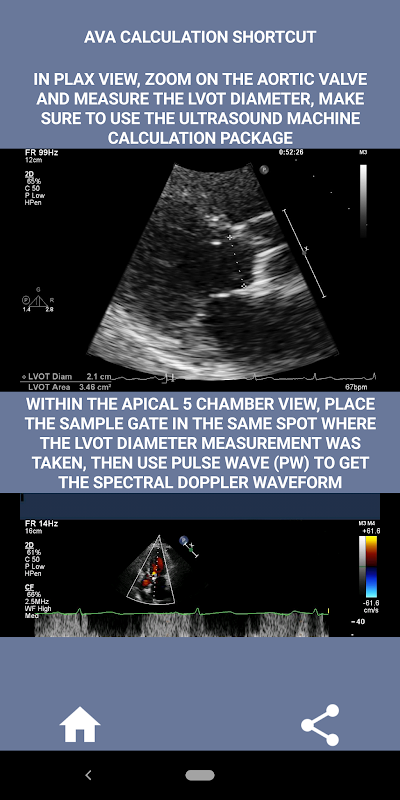

На мой взгляд, если собеседник может убедительно продемонстрировать этот навык, у него будет огромное преимущество перед другими кандидатами, которые слабы в этой области (это логично, поскольку обычно бывает так много случаев стеноза аорты). Если вы подаете заявку на должность кардиолога-сонографиста, кого-то, кому просто нужно освежить свои навыки, или студента эхолокации, то это приложение было разработано специально для вас практикующим кардиологом-сонографом. Простой и краткий, подходящий к делу, со множеством иллюстративных видеороликов, указывающих, где именно измерять (например, диаметр LVOT) и как проводить измерения в соответствии с опубликованными руководящими принципами ASE / ICAEL.